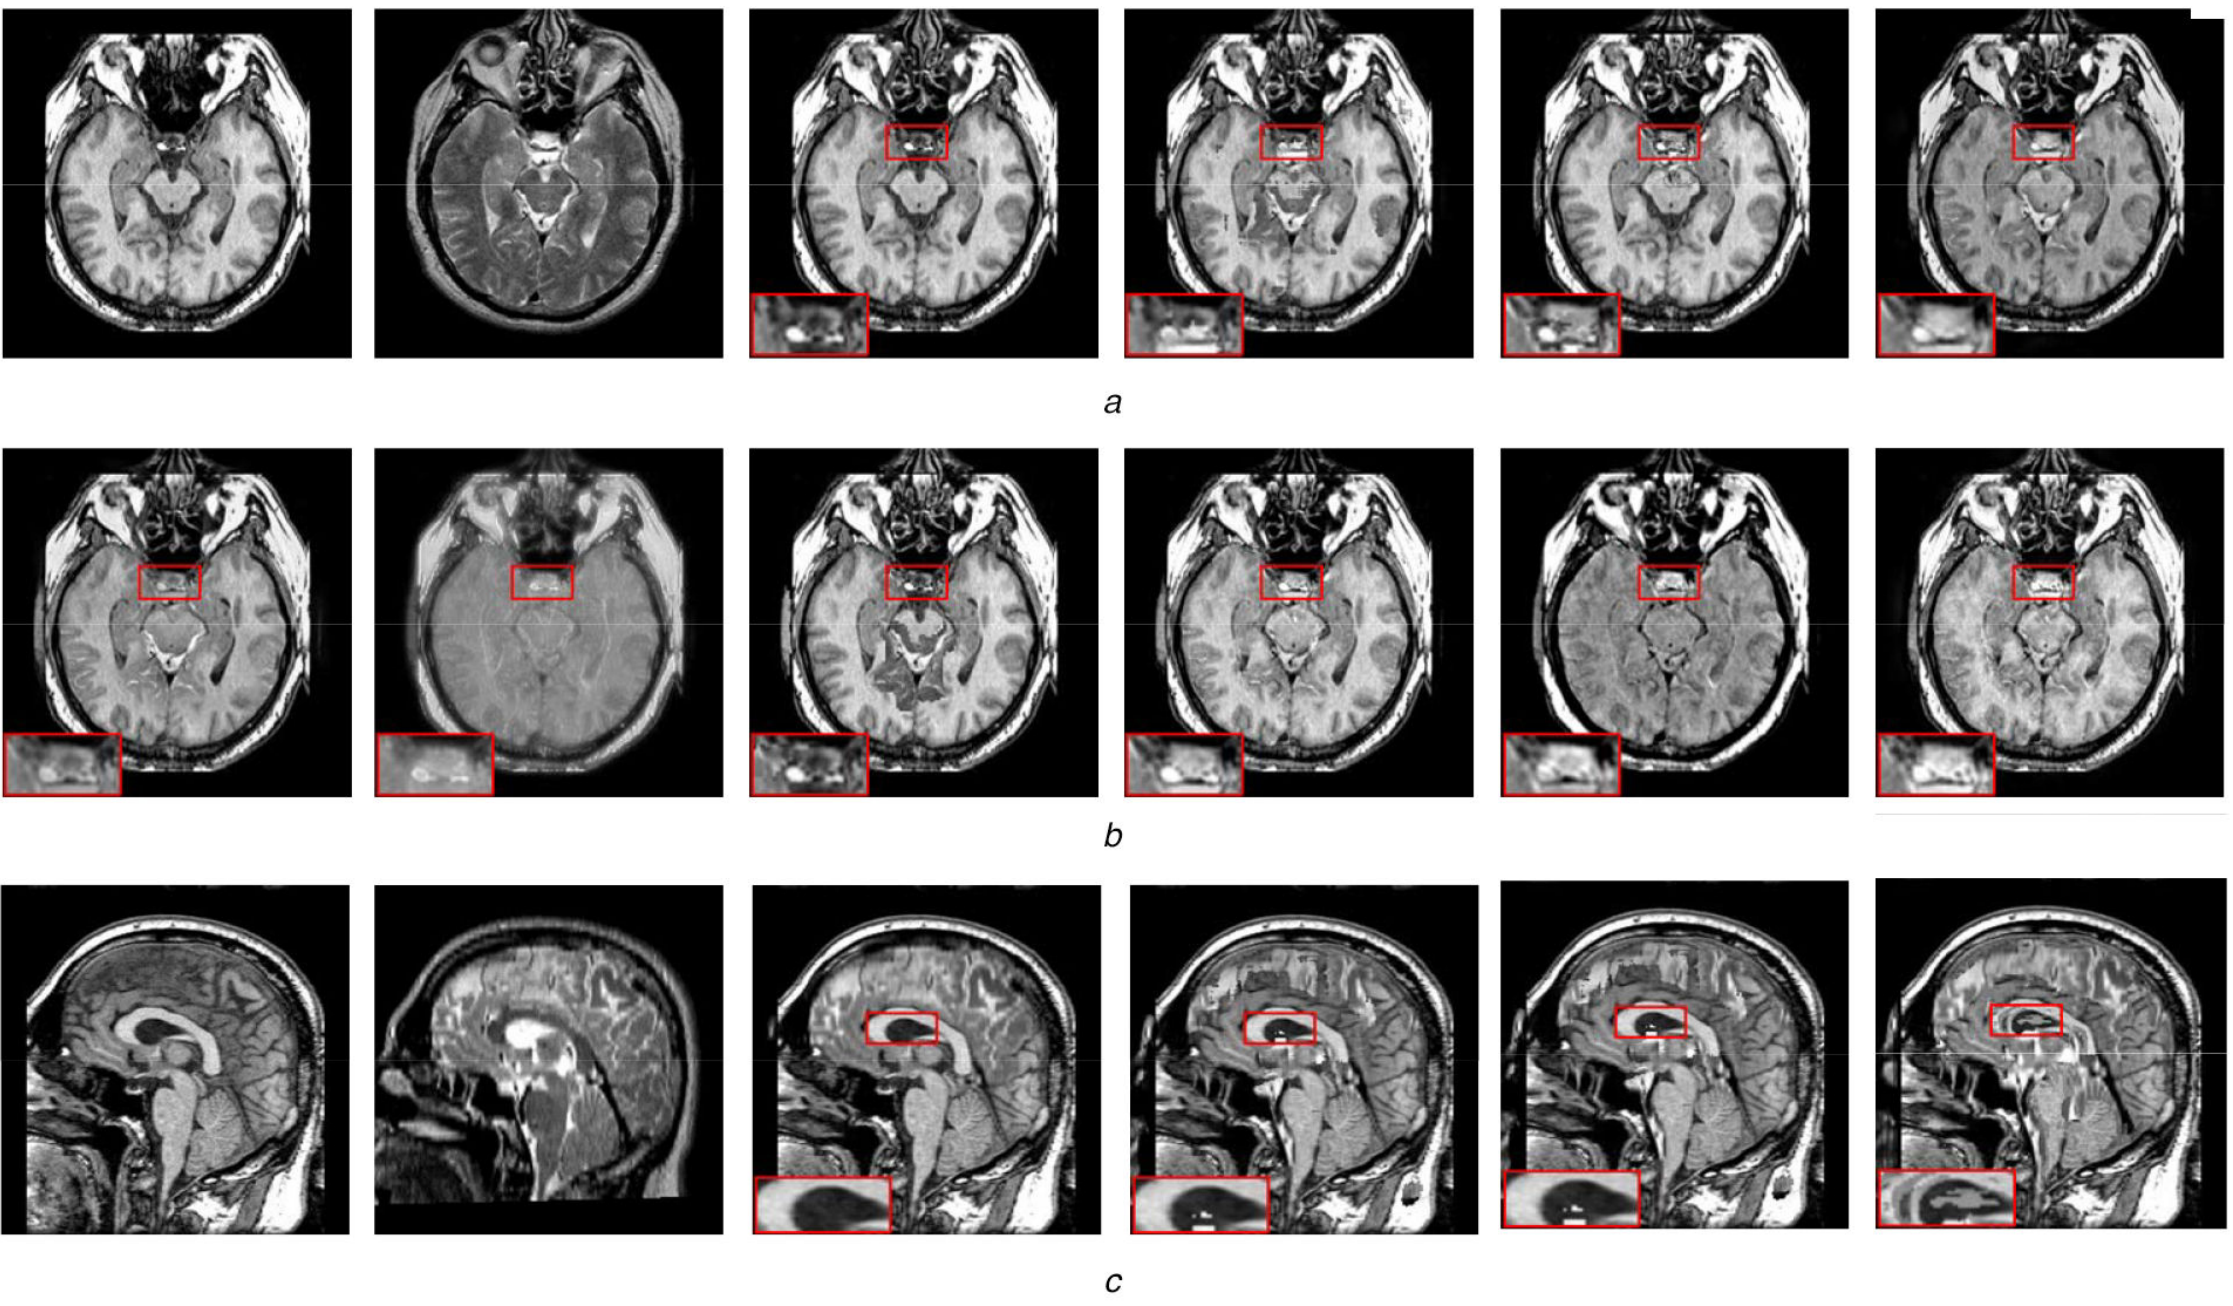

5)基于图像理解医学影像分析项目

基于图像理解的医学影像分析项目是一个多学科交叉的领域,涉及医学影像、数学建模、数字图像处理与分析、人工智能和数值算法等学科。这个项目的目的是利用计算机技术对医学影像进行自动分析和处理,以提高医生对疾病诊断的准确性和效率。基于图像理解的医学影像分析项目主要任务包括图像分类、分割、目标检测以及图像增强等。通过这些任务,医生可以更好地理解患者的病情,并制定更加精确的治疗方案。在实践中,基于图像理解的医学影像分析项目已经被广泛应用于各种疾病的诊断和治疗,手术导航和介入治疗等领域。目前该技术已成为一个重要的医疗辅助工具,帮助医生更加准确地诊断和治疗各种疾病,提高患者的医疗体验和健康状况。

图5 基于图像理解医学影像分析